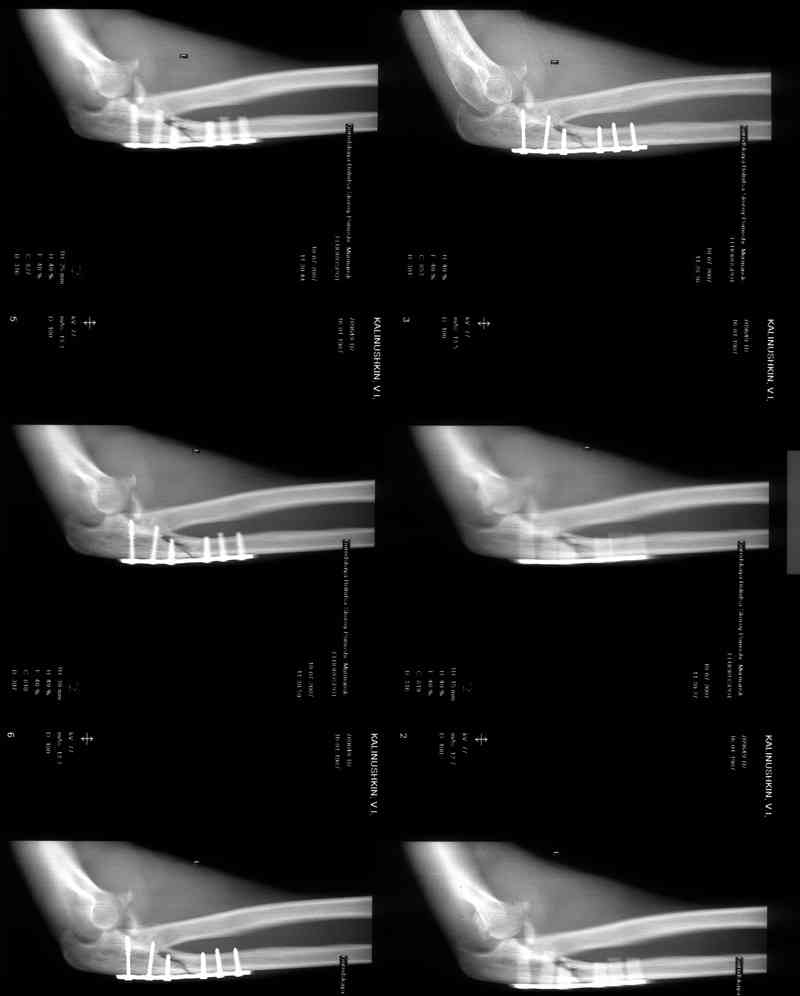

Со слов больного, травму получил при падении в подъзде на ступеньках.

Больной был прооперирован.Протеза головки лучевой у нас нет. Решили с локтевой костью пока ничего не делать. Выполнили операцию по востановлению связочного аппарата локтевого сустава(см.схему)- модфикация метода W.E.Spring,сухожилие мы фикстровали к винту на локтевой.

Естественно ревизия сустава и удаление рубцово-хрящевидных тканей.Затем наложили аппарат Илизарова с шарнирами. Первые 2 дня сустав был фиксирован трансартикулярно 2-мя спицами, затем спицы удалили. И больной начинает движения в аппарате.

Прилагаюся послеоперационные рентгенограммы.

Планиуем аппарат на 3-4 нед.

Что-то по снимкам ось шарниров с осью вращения локтевого сустава не сильно близко.